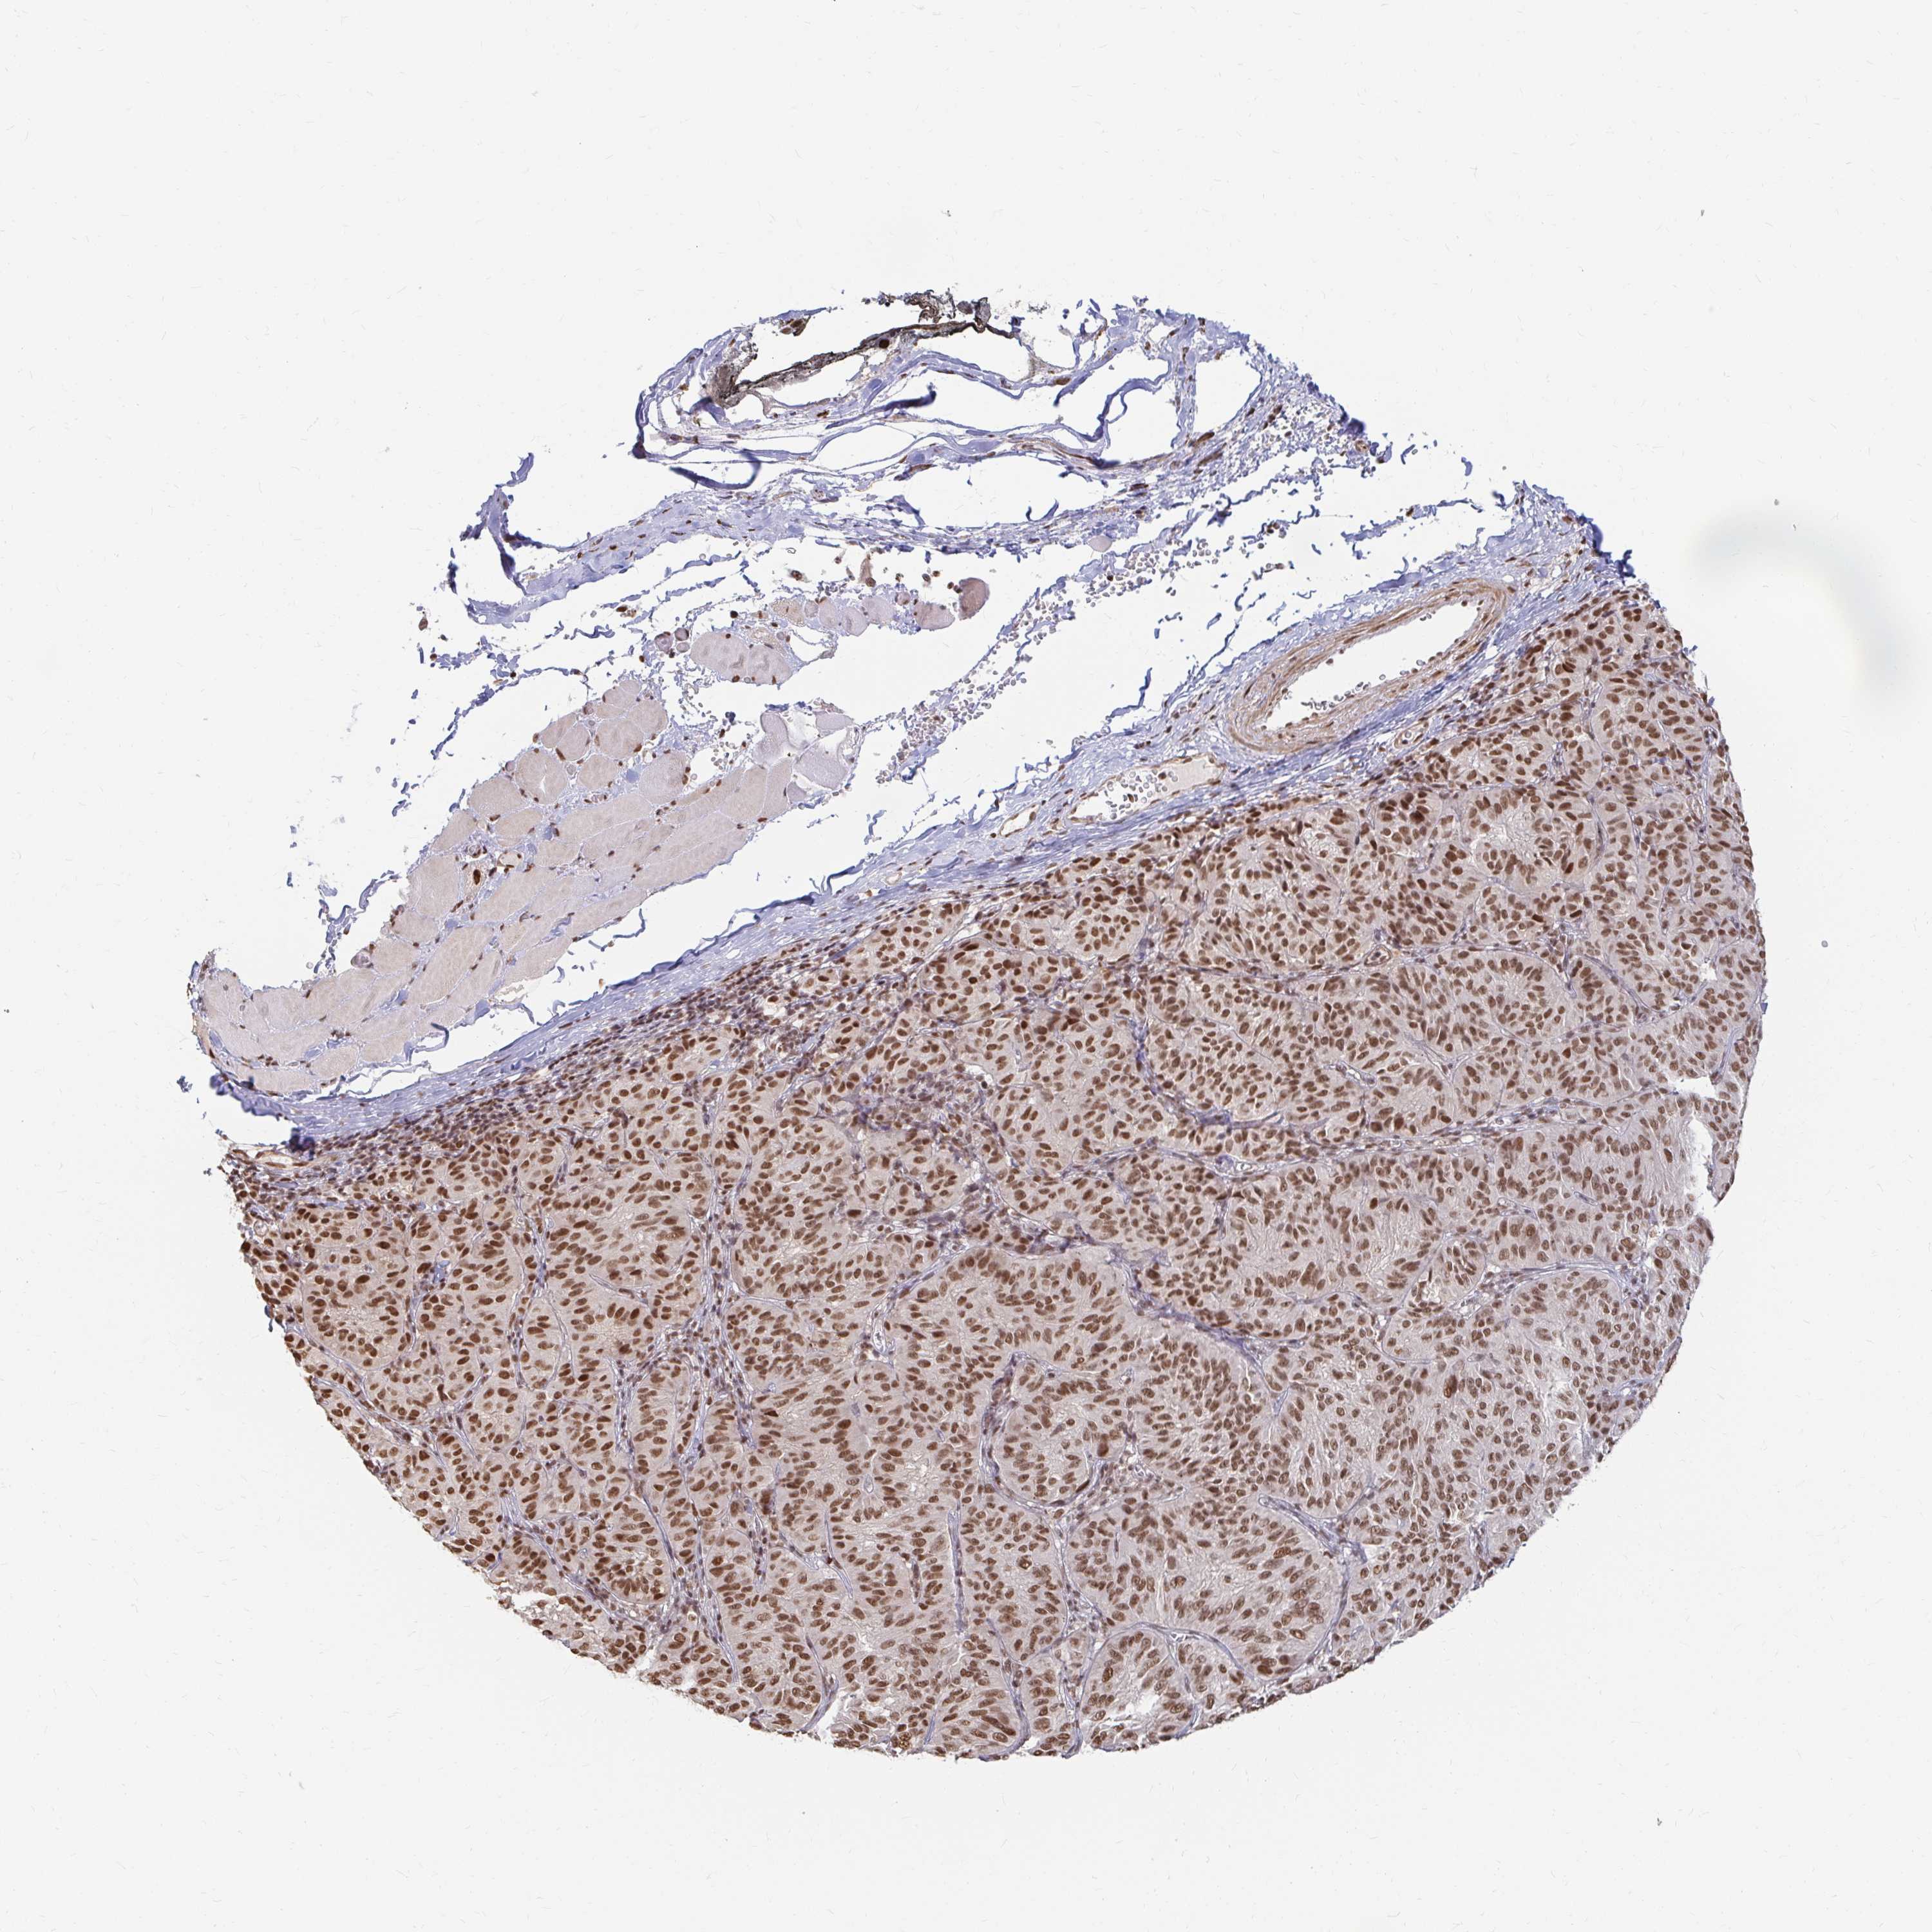

MELANOMA - Protein expressioni

A mouse-over function shows sample information and annotation data. Click on an image to view it in a full screen mode. Samples can be filtered based on level of antibody staining by selecting one or several of the following categories: high, medium, low and not detected. The assay and annotation is described here.

Note that samples used for immunohistochemistry by the Human Protein Atlas do not correspond to samples in the TCGA dataset.

Antibody stainingi

Antibody staining in the annotated cell types in the current human tissue is reported as not detected, low, medium, or high, based on conventional immunohistochemistry profiling in selected tissues. This score is based on the combination of the staining intensity and fraction of stained cells.

Each image is clickable and will lead to virtual microscopy that enables deeper exploration of all samples and also displays staining intensity scores, fraction scores and subcellular localization as well as patient and tissue information for each sample.

Antibody HPA041057

Antibody HPA058707

Antibody CAB011532

Staining

High

Medium

Low

Not detected

Intensity

Strong

Moderate

Weak

Negative

Quantity

>75%

75%-25%

<25%

None

Location

Nuclear

Cytoplasmic/membranous

Cytoplasmic/membranous,nuclear

Malignant melanoma, NOS

Malignant melanoma, Metastatic site